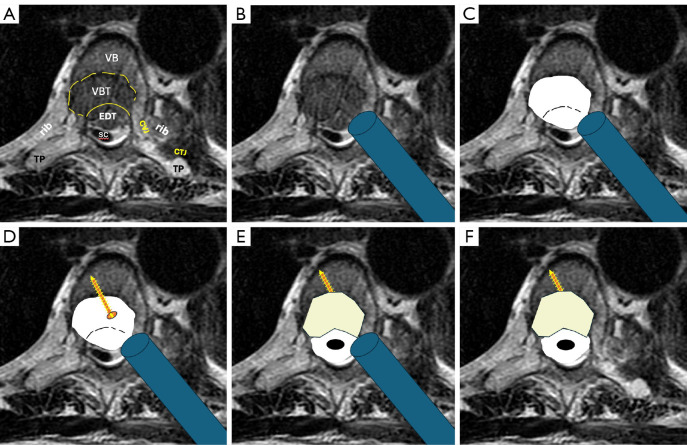

Abstract Image